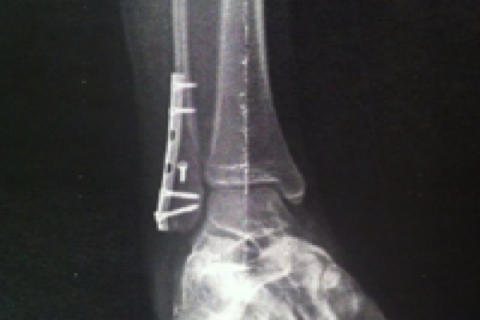

Die Operation ist gut gelaufen und Sonja ist seit dem Mittwoch wieder daheim. Vielen herzlichen Dank an alle für die moralische Unterstützung und das fleissige Daumendrücken. Auch wenn das Bein noch geschwollen ist, sollte es doch gut kommen.

Nur die Skisaison und das Tanzparkett dürften vorerst leider kein Thema sein :-(